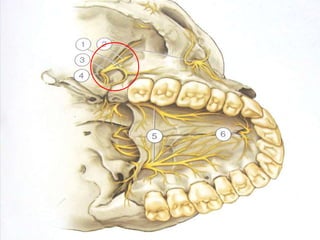

Within cranium In pterygopalatine fossa In infraorbital canal On face

IN PTERYGOPALATINE FOSSA

1. ZYGOMATIC NERVE

enters orbit through

inferior orbital

fissure ,

it gives 2 branches

within inferior orbital

fissure

Zygomaticotemporal Nerve

- Runs along lateral orbital wall

- Appears in infratemporal region

- Supplies skin of temporal region after

piercing temporal fascia 2 cm above the

zygoma.

- Gives communicating branch to lacrimal

nerve.